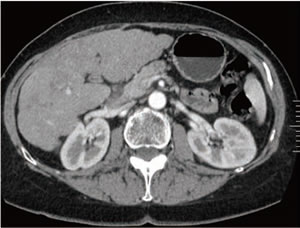

図5は、肝転移画像の比較で、以前使用していた16列CTとDiscovery CT750 HDでのシングルエナジー撮像画像、そしてRevolution CTのGSI Xtream 撮像画像を示したものである。GSI Xtream は低濃度コントラストの描出が優れている印象であり、前述したアーチファクト、ノイズ対策の恩恵が得られる部分である。

201710_voice_img_ct_01_07.jpg

図5: GSI Xtreamで撮影された臨床画像 1